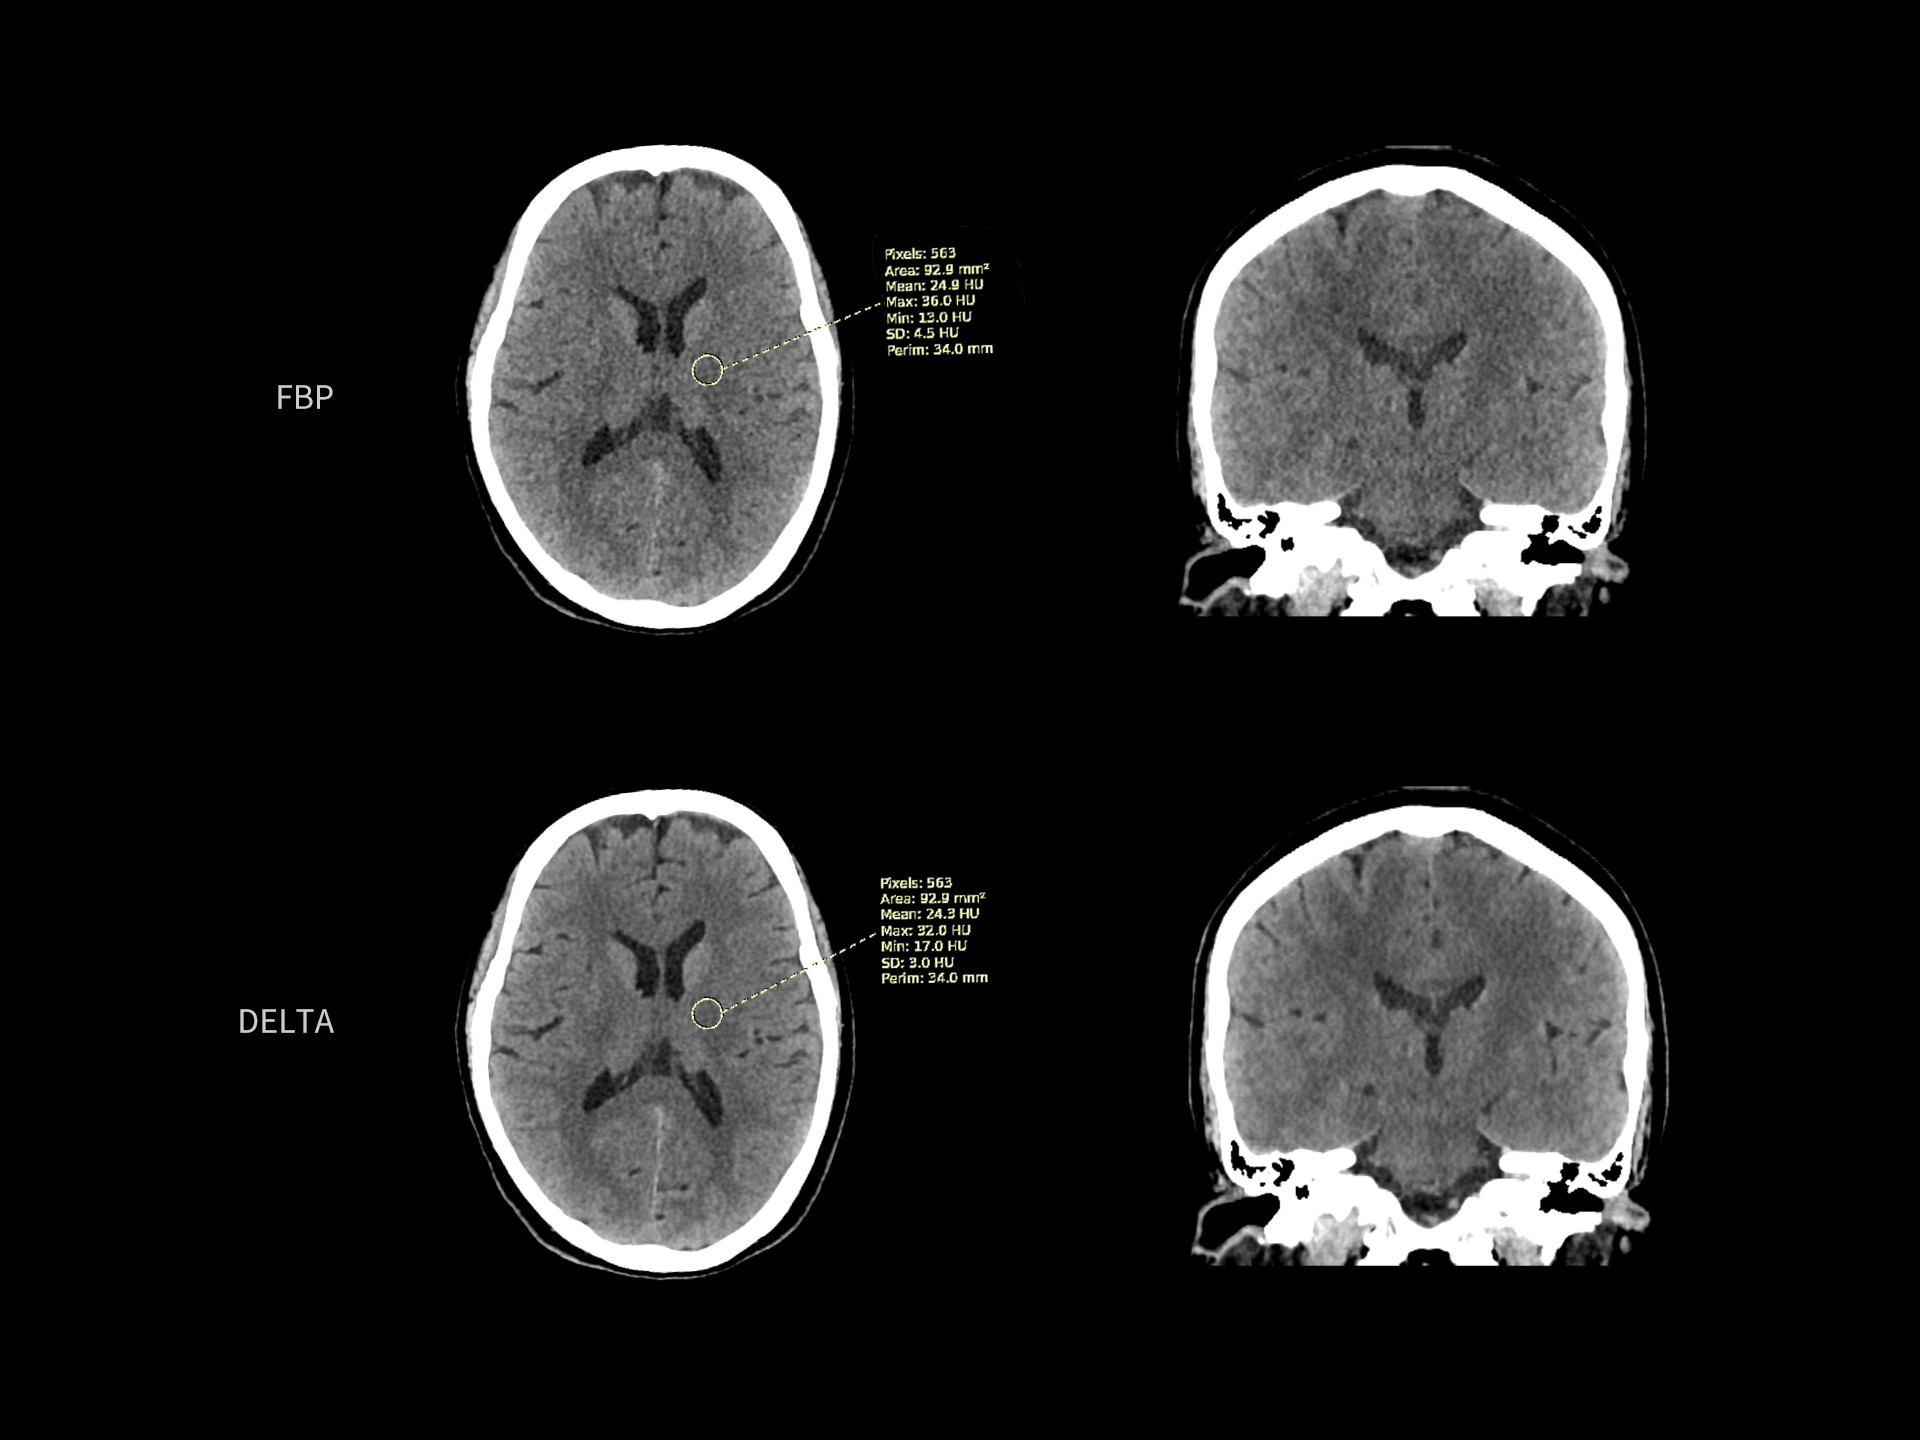

DELTA reduce zgomotul de imagine și îmbunătățește detectabilitatea contrastului redus

| Parametri scanare |

kV: 120 mAs: 285 CTDIvol: 45.8 mGy Doză efectivă: 1.7 mSv |

| Parametri reconstrucție |

Matrice: 512 × 512 Grosime secțiune: 1.0 × 0.8 mm HIR: H_SOFT_B Nivel DL-Denoise: 3 WW/WL: 80/35 |

| Contrast | — |

kV: 100 mAs: 130 CTDIvol: 7.568 mGy Doză efectivă: 0.54 mSv |

Matrice: 512 × 512 Grosime secțiune: 1.0 × 0.5 mm HIR: H_SOFT+ Nivel DL-Denoise: 3 WW/WL: 820/250 |

| Contrast | 350 mgl/ml 65 ml |

DELTA ridică standardul calității imaginii în toate dimensiunile

Spre deosebire de metodele convenționale precum Filtered Back-Projection (FBP) și Model-Based Iterative Reconstruction (MBIR), tehnologia DELTA oferă un echilibru optim între calitatea imaginii, doză redusă de radiații și viteză mare de reconstrucție.

Prin această performanță, DELTA stabilește un nou standard în imagistica CT.

Îmbunătățire de până la 163% a detectabilității contrastului redus (LCD)*

Performanță superioară a imaginii, cu o creștere de până la 163% a LCD la aceeași doză de radiații, pentru un diagnostic mai precis.

Îmbunătățire de până la 74% a rezoluției spațiale*

Performanță superioară a imaginii, cu o creștere de până la 74% a rezoluției spațiale la aceeași doză de radiații, pentru detalii mai clare și un diagnostic mai precis.

Reducere de până la 80% a dozei de radiații*

Menține aceeași detectabilitate a contrastului redus (LCD), oferind imagini de calitate la o expunere semnificativ mai mică pentru pacient.

Reducere de până la 98% a zgomotului de imagine*

Asigură imagini mult mai clare, menținând aceeași doză de radiații și îmbunătățind semnificativ acuratețea diagnosticului.